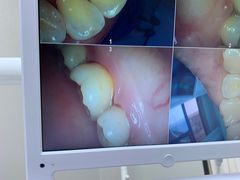

• 牙博士口腔(杨浦店)

• -牙博士口腔(杨浦店)

xksy_3340 | 20-08-01